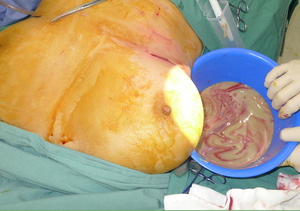

A 53-year-old woman presented with two months of right breast swelling and fevers with a background of bilateral free PAAG filler augmentation in China 14 years earlier. MRI showed free prosthetic material in subglandular and subpectoral pockets on both sides without parenchymal lesions (Figure 1). On examination she had marked swelling and mild erythema of the right breast with elevated inflammatory markers. The patient was taken to theatre the same day for evacuation of the prosthetic filler. Via bilateral infra-mammary incisions, 900 ml of purulent material was evacuated from the right breast (Figure 2) and 300 ml PAAG filler removed from the left breast (Figure 3). Tissue culture, swab culture and capsule histopathology demonstrated scant mix of skin flora. Mycobacterial PCR for tuberculosis was negative. Capsule histopathology from both sides showed fibrous pseudocapsule with extracellular foreign body material and a mixed inflammatory cell infiltrate. The patient completed a six-week oral antibiotic regime and made an uncomplicated recovery.